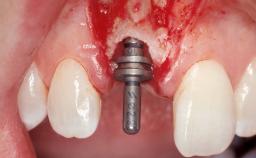

A 33-year-old female patient presented with an upper left central incisor that required extraction after a failed endodontic therapy. The tooth had been traumatized when the patient was a teenager and had undergone several endodontic treatments, including two apicectomy procedures. The patient was in good health and did not smoke. Clinical examination showed that the patient had a high lip line. In full smile, the gingival margins of the upper teeth were visible to the first molars. The gingival margins of central incisors 11 and 21 were only just showing. Examination of tooth 21 confirmed that the tooth was mobile and had hypererupted by 1 mm.

Placement Protocol Immediate implant placement

Tooth Site Maxillary incisor or canine

Socket Morphology Single-root socket